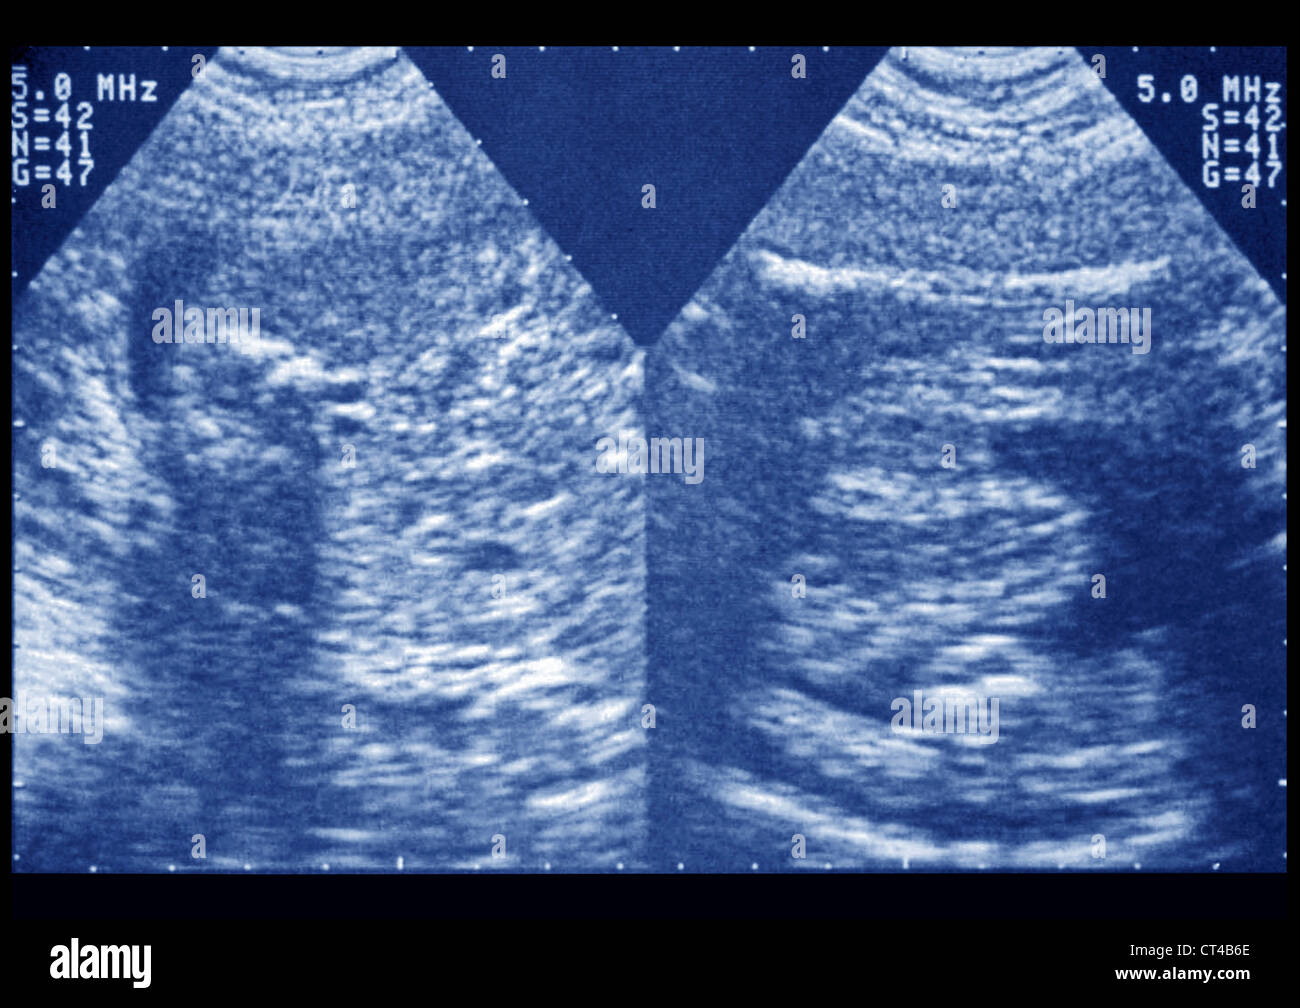

KIDNEY PTOSIS, ULTRASONOGRAPHY Stock Photo Alamy Floating Kidney And Renal Ptosis nephroptosis, also known as floating kidney and renal ptosis, is a condition in which the kidney descends. intravenous pyelography performed in supine and upright positions demonstrating >5 cm craniocaudal. nephroptosis, also known as floating kidney and renal ptosis, is a condition in which the kidney descends more than two vertebral. nephroptosis, also known as a floating. Floating Kidney And Renal Ptosis.